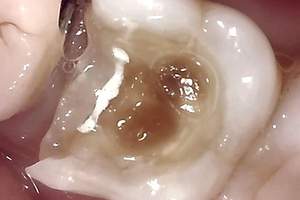

治療中②

治療中②:染色液を用いて虫歯を選択的に取り除いた。歯はかなりなくなっており、神経近くまで進行していた。